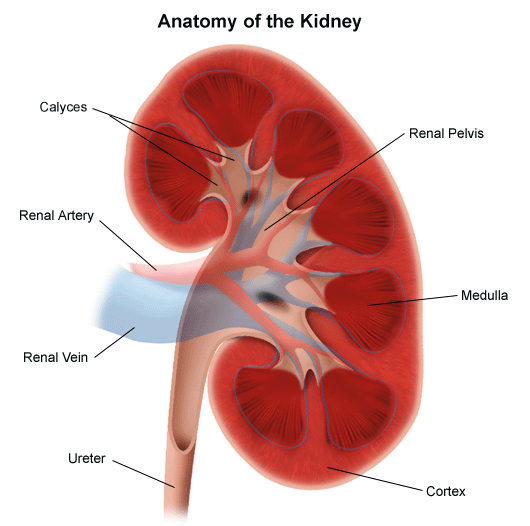

A vesék kiválóan vizsgálhatóak ultrahangal. Bab alakú páros szerv ami a has hátsó részében helyezkedik el kétoldalt. Ellentétben a hasnyálmirigyel, viszonylag könnyen vizsgálható szerv, hiszen nem fedik csontok. A bordakosár alatt helyezkednek el, vagy ha pozíciójuk kissé magasabban is van, egy mély légvétel után általában jól látótérbe hozhatók. Tovább segítheti a vizsgáló orvost, hogy nem csak előlről, hanem a has oldalsó része felől, vagy ha szükséges (pl. kifejezetten gázos belek esetén) a hát felől is megkísérelhető a vizsgálat.(1. kép)

2. kép:

Vese

Egy sematikus ábrát láthatunk a veséről. A vese parenchyma 2 részből áll, a velő (medulla) és a kéreg (cortex) állományból. A vizelet a vesemedencében gyűlik össze (pelvis), ahonnan a húgyvezetéken (ureter) keresztül távozik a hólyag irányába. Láthatjuk, hogy a vesemedencében relatív nagyobb tér áll rendelkezésre mint a hugycsőben, ami miatt a fent keletkezett nagyobb kövek nagyobb eséllyel akadhatnak el a szűkebb húgycsőben. A vesének azt a részét ahol a vizeletelvezető rendszer kilép a veséből kapunak nevezik. A vesét ellátó erek is itt lépnek be illetve ki a veséből.